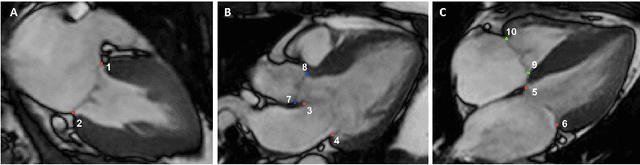

Abstract:Valve annuli motion and morphology, measured from non-invasive imaging, can be used to gain a better understanding of healthy and pathological heart function. Measurements such as long-axis strain as well as peak strain rates provide markers of systolic function. Likewise, early and late-diastolic filling velocities are used as indicators of diastolic function. Quantifying global strains, however, requires a fast and precise method of tracking long-axis motion throughout the cardiac cycle. Valve landmarks such as the insertion of leaflets into the myocardial wall provide features that can be tracked to measure global long-axis motion. Feature tracking methods require initialisation, which can be time-consuming in studies with large cohorts. Therefore, this study developed and trained a neural network to identify ten features from unlabeled long-axis MR images: six mitral valve points from three long-axis views, two aortic valve points and two tricuspid valve points. This study used manual annotations of valve landmarks in standard 2-, 3- and 4-chamber long-axis images collected in clinical scans to train the network. The accuracy in the identification of these ten features, in pixel distance, was compared with the accuracy of two commonly used feature tracking methods as well as the inter-observer variability of manual annotations. Clinical measures, such as valve landmark strain and motion between end-diastole and end-systole, are also presented to illustrate the utility and robustness of the method.